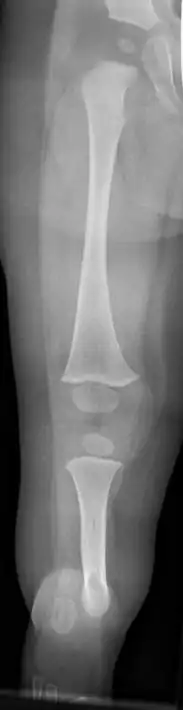

| Fibula hemimelia in patient affecting right side | |

Fibular hemimelia or longitudinal fibular deficiency is "the congenital absence of the fibula and it is the most common congenital absence of long bone of the extremities."[1][2] It is the shortening of the fibula at birth, or the complete lack thereof. Fibular hemimelia often causes severe knee instability due to deficiencies of the ligaments. Severe forms of fibula hemimelia can result in a malformed ankle with limited motion and stability. Fusion or absence of two or more toes are also common.[3] In humans, the disorder can be noted by ultrasound in utero to prepare for amputation after birth or complex bone lengthening surgery. The amputation usually takes place at six months with removal of portions of the legs to prepare them for prosthetic use. The other treatments, which include repeated corrective osteotomies and leg-lengthening surgery (Ilizarov apparatus), are costly and associated with residual deformity.[4]